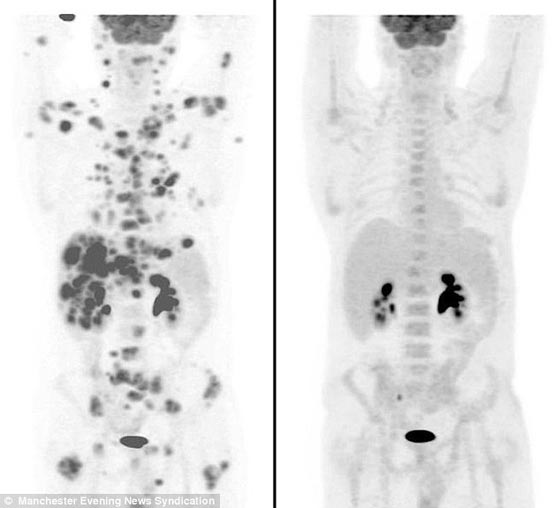

وفوجئ الأطباء في مدينة مانشستر، شمالي إنجلترا، بأن المريض إيان بروكس البالغ من العمر 47 عاماً، الذي يعاني من واحد من أسوأ أنواع السرطان وأسرعها انتشاراً، ويؤثر على جهاز المناعة في الجسم، بأنه تمكن من التغلب على المرض بشكل مذهل بعد أن تعاطى دواء يُدعى (Brentiximab Vedotin). وبحسب ما أوردت جريدة "ديلي ميل" البريطانية، الثلاثاء، فقد أظهرت صور ضوئية لجسد إيان بروكس اختفاء أكثر من 70 ورما سرطانيا قاتلا من جسده وذلك خلال 12 أسبوعاً على تناوله العلاج، في استجابة مذهلة وغير مسبوقة لهذا العلاج.

وأشار إلى أن الطبيب المختص الذي يعالجه بالمستشفى كان مبهوراً جداً بالنتائج التي حققها من خلال العلاج، مضيفاً: "كان لدي أكثر من 70 ورما قاتلا في جسدي وتم القضاء عليها جميعاً، لدي شعور لا يمكن وصفه". وتشير الإحصاءات الطبية في بريطانيا إلى أنه يتم تسجيل نحو 1500 حالة من مرض "الليمفوما" سنوياً، إلا أن حالة بروكس تعتبر من الأنواع النادرة المرتبطة بهذا المرض.